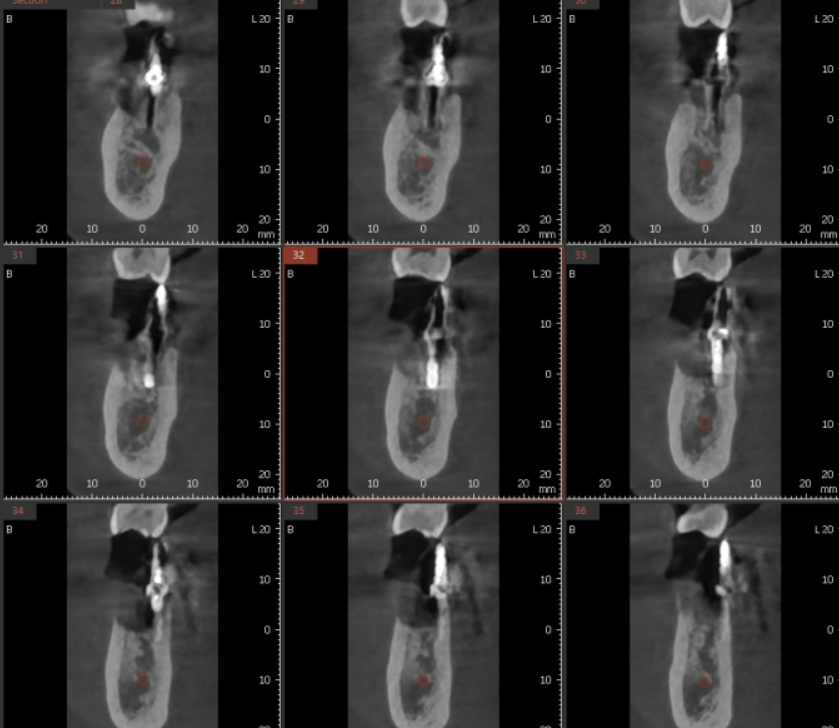

최근에는 기술의 발전으로 뼈를 자세히 분석이 가능하지만

사실 x-ray 상에서는 정확하지 않습니다.

잇몸을 열어 눈으로 직접 보기 전까지는요!!